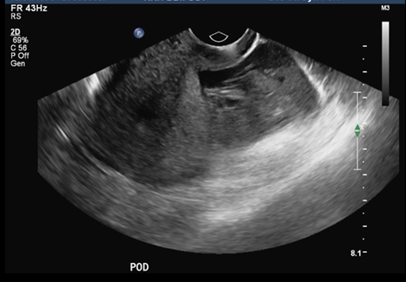

Urine hCG done in A&E was positive. Her haemoglobin was 12.4 g/dL. Her serum Beta hCG level was 825.1IU/L. Total WBC count and urinalysis was normal. A transvaginal ultrasound scan showed empty endometrial cavity (Figure 1) and moderate hemoperitoneum in the pouch of Douglas (Figure 2). There was no obvious adnexal mass seen. No corpus luteum was noted.

Figure 2: Hemoperitoneum in pouch of Douglas.

In view of severe pain in abdomen, hCG levels 825.1IU/L and ultrasound suggestive of moderate hemoperitoneum, the diagnosis of ruptured ectopic pregnancy in contralateral tube was suspected.